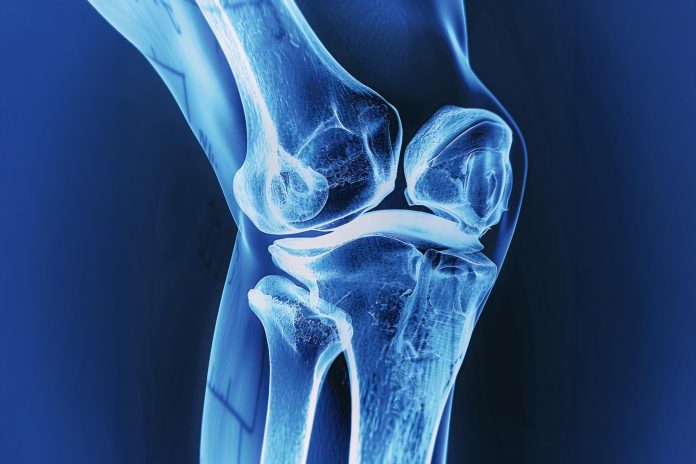

Εμπνευσμένοι από το πώς τα οστά επουλώνονται φυσικά, οι ερευνητές κατασκεύασαν μια υδρογέλη με δομή λέιζερ που θα μπορούσε μια μέρα να αντικαταστήσει τα συμβατικά οστικά εμφυτεύματα. Τα οστά που έχουν σπάσει σε ένα ατύχημα (σκι) συχνά επιδιορθώνονται χωρίς ιατρική παρέμβαση. Ωστόσο, όταν ένα διάλειμμα είναι ιδιαίτερα σοβαρό ή ένας όγκος των οστών πρέπει να αφαιρεθεί χειρουργικά, οι γιατροί μπορούν να τοποθετήσουν ένα εμφύτευμα για να σταθεροποιήσουν την περιοχή […]